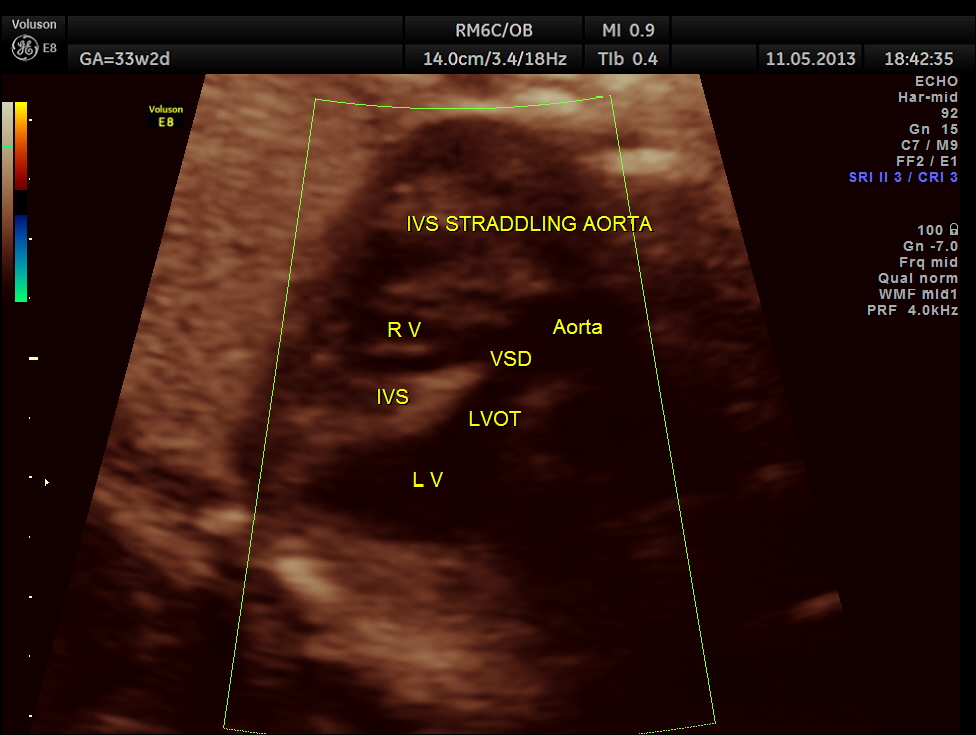

the LV Outflow tract view was more revealing . The IVS is seen straddling the aorta .

the next few pictures show the straddling of the aorta by the inter ventricular septum.